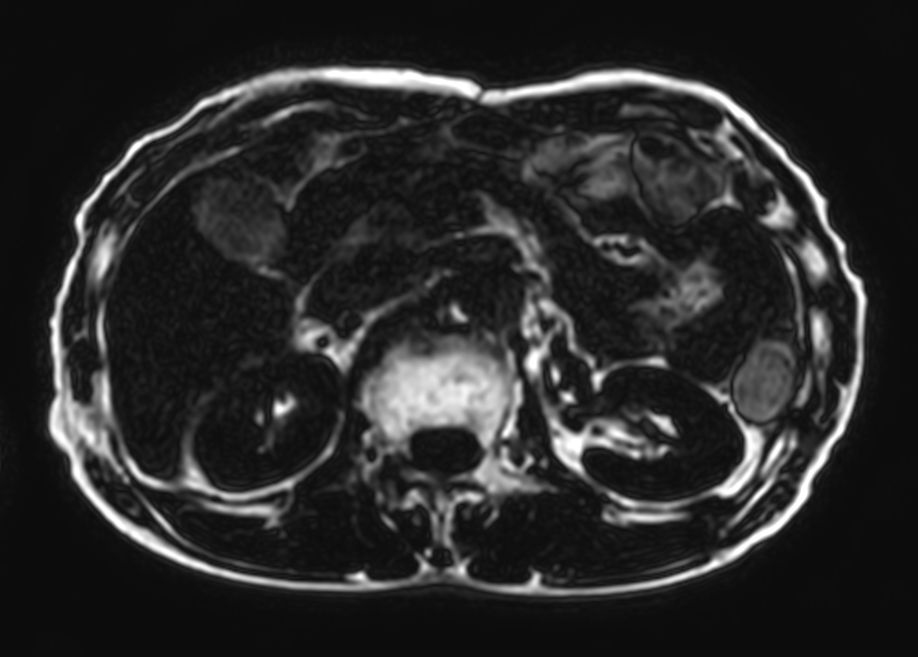

T2w TSE SSh - Respiratory triggering